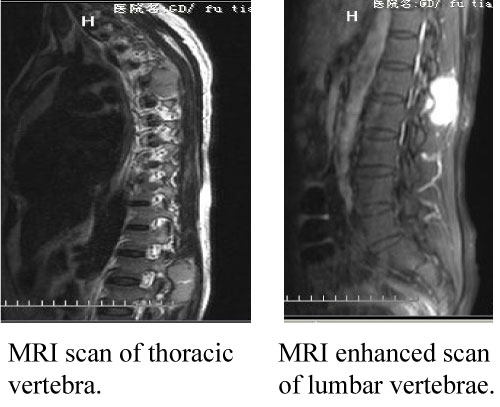

7 years after the right sphenoid ridge meningioma surgery, the patient presented to us again with back pain for 2 months. The magnetic resonance imaging (MRI) and CT (2013) (Figure 8) showed the patient had a surgical scar at the right frontal temporal, a frontal temporal skull defects, and the tenderness and percussion pain on thoracic. The limb muscle strength was level 5, the bilateral limb skin' feeling was normal, the limb muscle tension was not high, and the bilateral Babinski, Brudzinski, and Klinefelter signs were negative. The CT, MRI and CTA examination showed the intracranial meningeal tumor recur again and metasted to vertebra thoracalis and vertebra lumbalis (Figure 9). Three surgery were taken for the recurrence and metastases of the meningeal tumor. Firstly, thoracic tumor resection and thoracic pedicle screw fixation were taken for the thoracic metastasis on general anesthesia (Figure 10) and then the second operation was perform for the resection of the recurrence of meningeal tumor; At last, the lumbar tumor resection and lumbar pedicle screw fixation were taken for the lumbar metastasis on general anesthesia (Figure 11) and the tumor was further diagnosed to be intracranial meningeal hemangiopericytoma.

Figure 9: The MRI test of vertebrae. View Figure 9